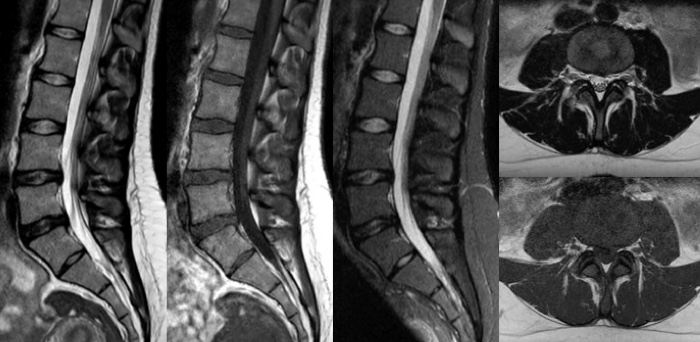

High quality diagnostic imaging

Our lightest Breeze coils bring versatility and create consistent high quality images for any anatomy.

Turn images into answers – 50% faster

Put time on your side with Compressed SENSE to reduce scan time up to 50%2 with virtually equal image quality. Create exceptional MR images with 60% higher resolution for confident diagnosis.

Quality images for quality diagnoses

Our lightest Breeze coils bring extraordinary versatility to imaging challenging anatomies and the smallest joints. A large 55cm field-of-view and premium SNR add to the exceptional image quality.